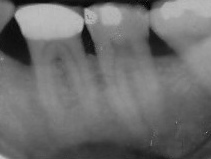

This is an example of an bone defect. The area was repaired and the xray on the bottom is a 23 year followup of a case we treated.

After (2013)